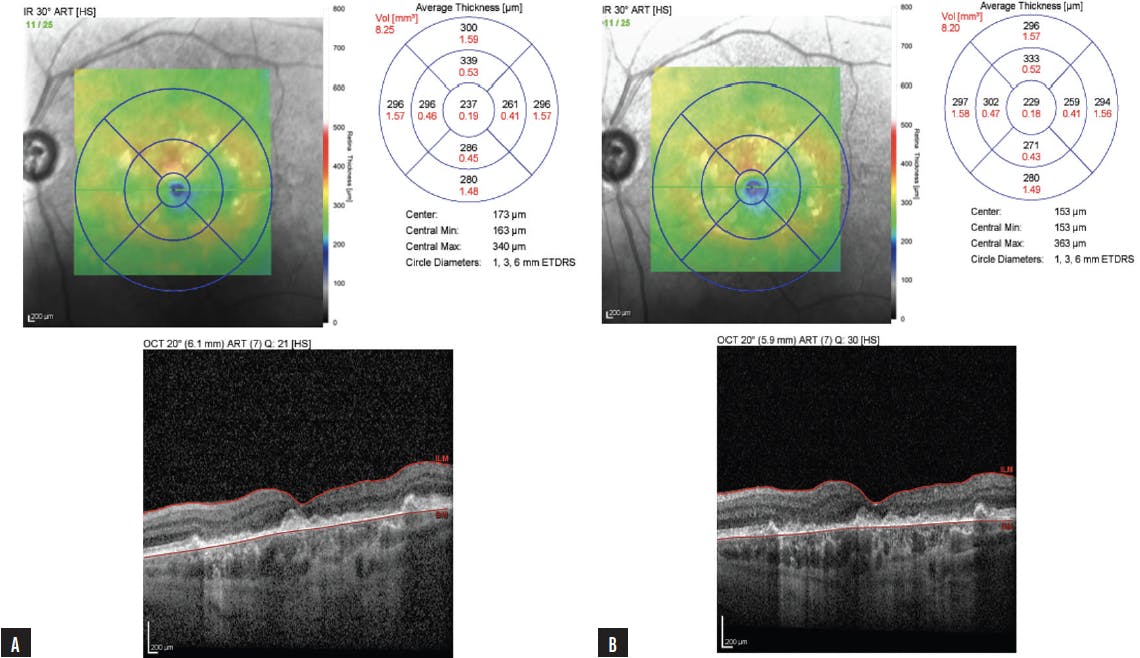

Dr. Almeida: In this fairly straightforward case of GA, a patient presented to my clinic complaining of visual decline. OCT imaging and color fundus photography depicted a unifocal lesion with slight foveal involvement (Figure 9). This patient wanted to act quickly to delay future loss of vision and opted for monthly dosing with avacincaptad pegol. After three monthly doses, OCT imaging showed that GA progression was not evident (Figure 10). The patient was happy with the lack of disease progression and has reported a desire to continue monthly therapy.

Figure 9. A patient who presented with a complaint of visual decline showed a unifocal lesion nearing the fovea on OCT imaging (A) and color fundus photography (B).

Figure 10. After 3 monthly doses with avacincaptad pegol, this patient’s GA had not noticeably progressed on OCT imaging.

In a separate case, a patient was diagnosed with GA in March 2023, based partly on OCT imaging (Figure 11A). I observed limited foveal involvement. I asked them to return for several monitoring visits to assess the rate at which GA was progressing in this patient. The patient was amenable to treatment with avacincaptad pegol and wanted to initiate treatment despite the limited progression observed during the monitoring period. After three monthly doses of avacincaptad pegol, I noted limited changes in their eyes (Figure 11B).

Figure 11. OCT imaging on presentation was used in the diagnosis of GA (A). After 3 monitoring visits, the patient began treatment with avacincaptad pegol. OCT imaging after the third injection of anti-complement therapy showed that the patient’s disease had progressed very little (B).